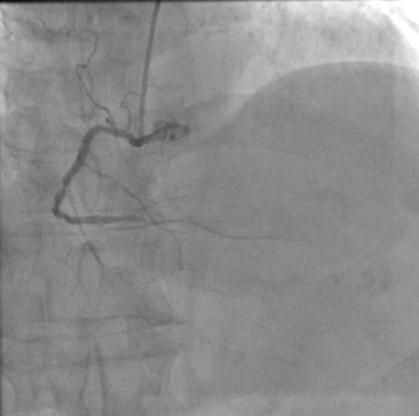

造影图:

造影显示提示前降支严重狭窄、回旋支次全闭塞、右冠慢性闭塞。

先后分期完成右冠及左冠PCI手术,但右冠CTO病变PCI手术术中出现开口夹层,一直撕裂至后三叉,且导丝位于假腔内。